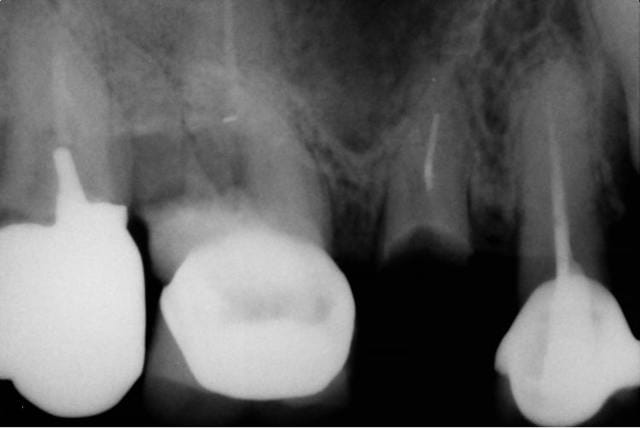

bon comportement de l'axiome en sous sinusien:

bonne sensation de compression, et stabilité primaire excellente, malgré le peu de volume osseux.